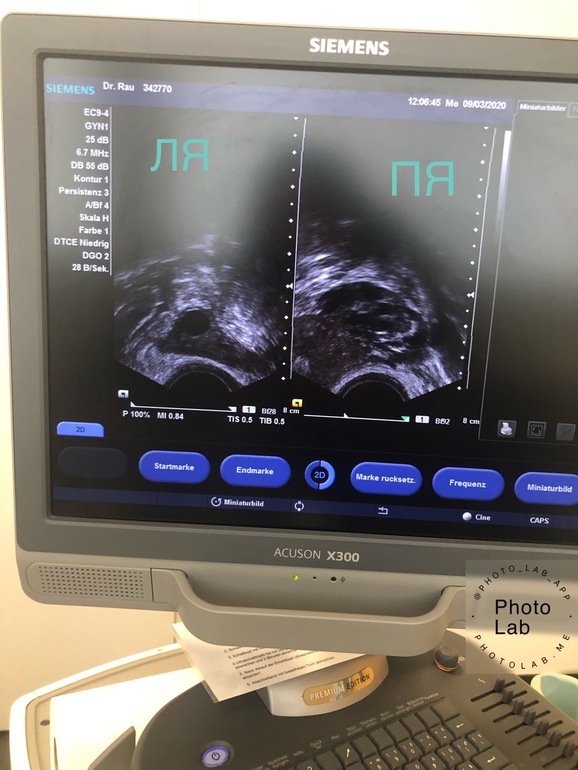

Доминантный фоликул?

Слишком большой фолликул для этого дня. Если это и ранняя овуляция то эндометрий под него не успеет созреть

Эндометрий был 6 мм. А может быть, что он замедлится в росте и с овулирует как обычно? Сейчас 9 дц, только начал появляться ЯБ. Спасибо

У меня сегодня 5 дц, в ЛЯ такой красивый ДФ, хотя ре сказала что рано его считать ДФ и даже не измерила 🤦🏽‍♀️🤬 Вот я сфоткала, красавец 😅 Но у меня и на 10 дц О бывает. Цикл 24-27 дней...